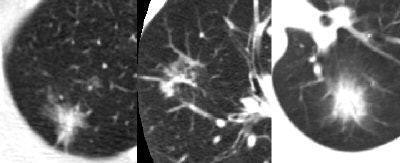

![]() |

| Part-solid nodules, above, are far more likely to be malignant than either solid or nonsolid nodules. |